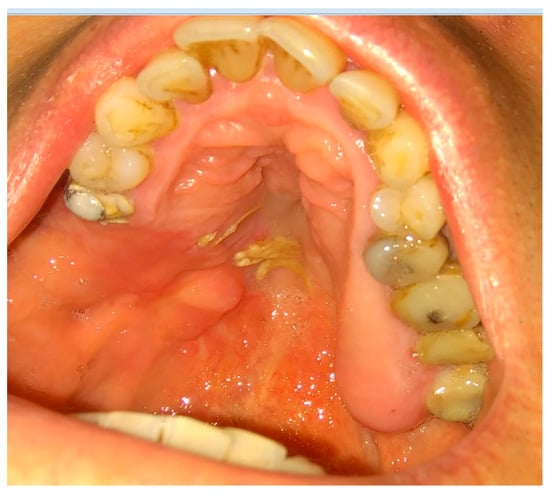

The rotation of the palatal flap can be used to solve some problems with the closure without buccal depth loss and esthetic function reduction. A full-thickness flap that contains the palatal artery is a good option to close an oro-antral communication. However, this procedure creates great morbidity and requires a long post-operative care period of the donor site on the palate. Flexibility possibilities of the palatal flap are limited, which forces the surgeon to create a large incision to assure the rotation of a sufficient amount of tissues. Second, the palatal defect heals via granulation, which is also troublesome for the patient. The location on the vestibular sulcus of the maxillary alveolar bone and the large size of the lesion support the choice of the pedicled buccal fat pad flap technique [21]. In some cases of bigger maxillary sinus wall deficiencies, the suturing can be troublesome, especially when it causes severe buccal narrowing or is sutured with tension. A free-of-tension suturing of any oroantral communication is easily achieved with the BFP and can be easily used for suturing in any dental surgery (Figure 1, Figure 2, Figure 3 and Figure 4).

Figure 2. The bone defect with visible buccal cortical bone loss. In this case, when the patient is not willing to undergo any dental implant rehabilitation, it is possible to suture the BFP in a double-layer technique to fully close the bone deficiency and cover it with a sliding muco-periostal flap.